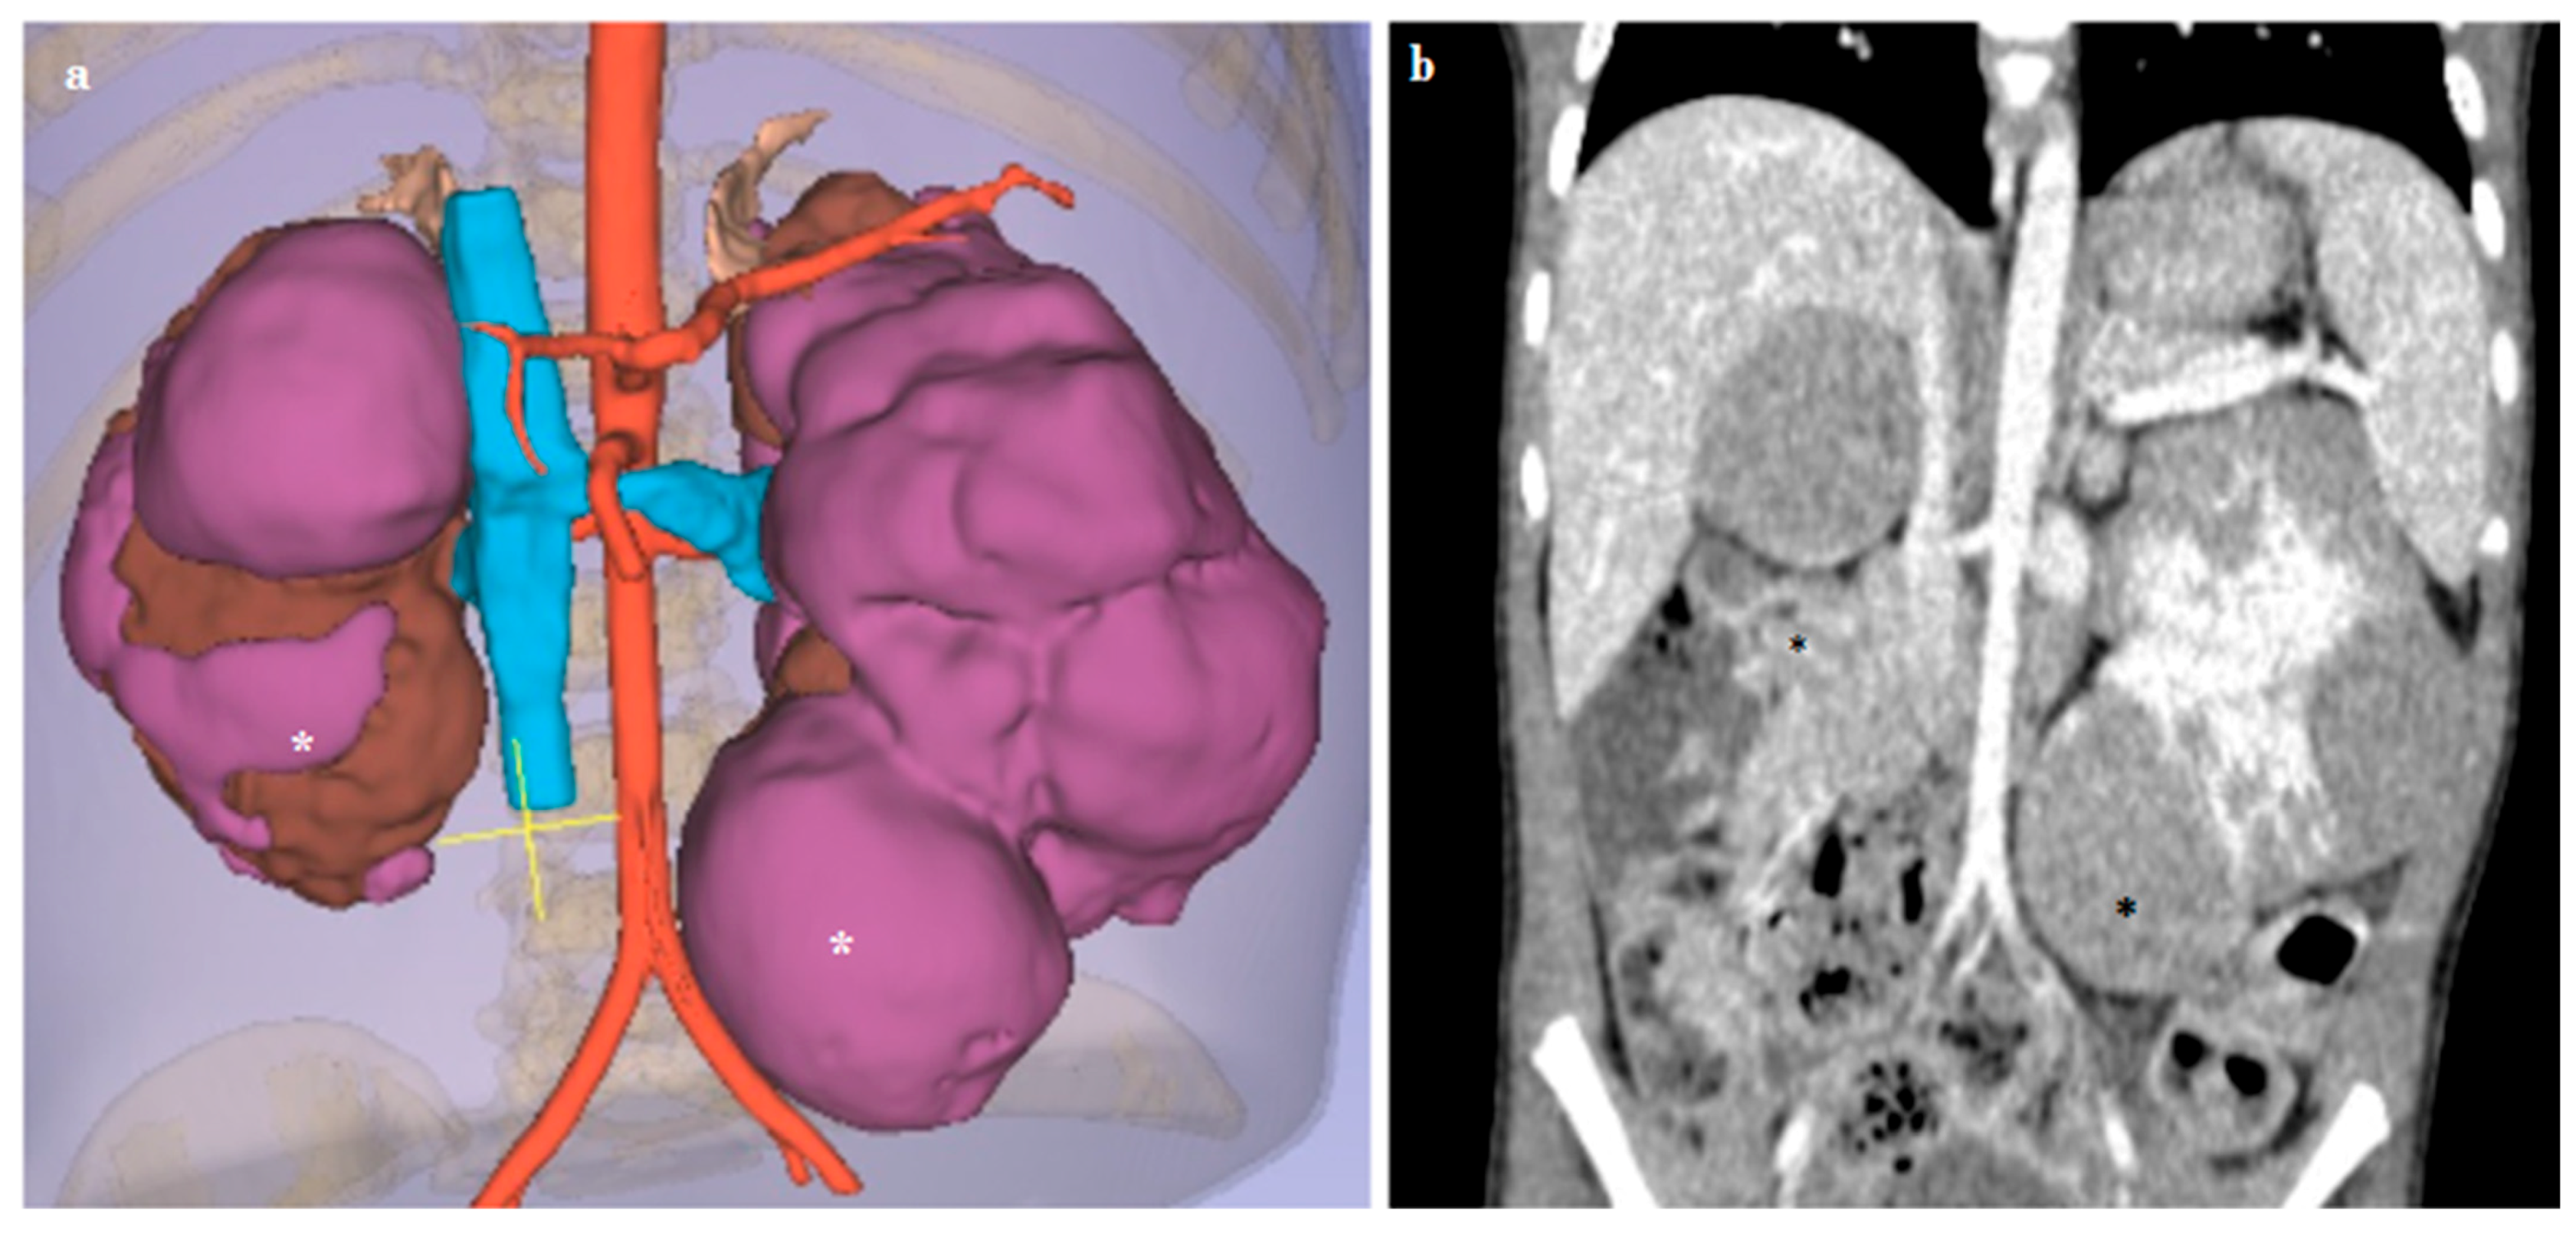

3.3. Kidney Lesions and Congenital Anomalies